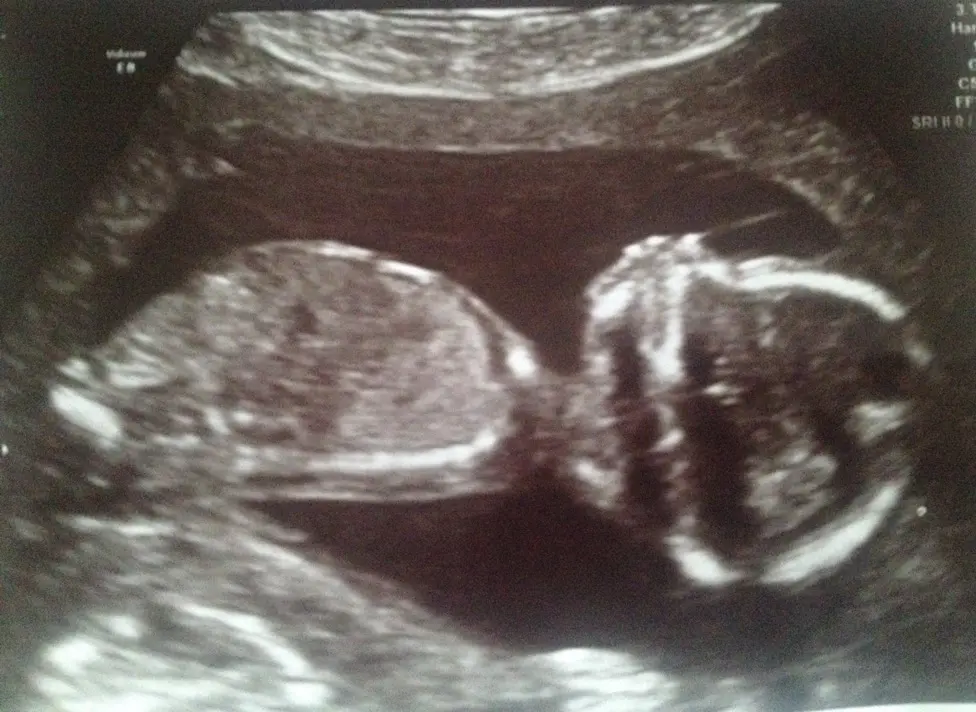

Most of you may know that I’m expecting a baby! Mainly thanks to the ridiculous amounts of blogs I’ve posted on Pregnancy Nutrition as well as from my work with Plant Based Pixie and the podcast I did with Laura Thomas.

My baby is due on the 3rd June (eeekkk) and so this little post is just to let you know that – although I fully intend to work in some capacity – I will be taking some time out, especially initially to be with my baby. Please bear with me during this time. I’m lucky enough to have people helping me out by posting my blogs and helping me to maintain social media presence to some extent. I’ll be tapping into these every now and then myself, but I’ll also have some people running them for me in the near future.